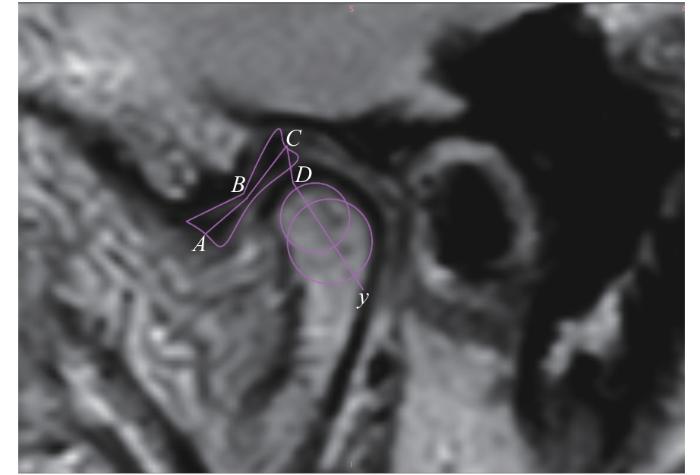

参考ZHANG等22提出的测量盘髁距离及关节盘长度的方法。闭口位时,A点为关节盘前带前缘的中点,B点为关节盘中间带的中点,C点为关节盘后带后缘的中点,关节盘的长度即为AB+BC;于髁突头的位置画2个内切圆,2个圆心的连线标记为髁突头部的长轴yy轴与髁突顶部的交点记为DCD之间的距离即设为盘髁距离(图4)。

图4

图4   盘髁距离及关节盘长度的测量

Note: An oblique sagittal PDWI image. A—the midpoint of the anterior edge of the anterior band of the articular disc; B—the midpoint of the intermediate zone of the articular disc; C—the midpoint of the posterior edge of the posterior band of the articular disc; y—the long axis of the condylar head; D—the intersection of y-axis with the condyle; AB+BC—the length of the articular disc; CD—the disc-condyle distance.

Fig 4   Measurement of disc-condyle distance and articular disc length